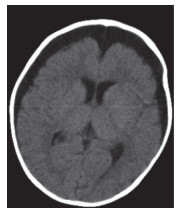

入院时实验室检查结果显示,(1)血常规:白细胞17.9×109/L,中性粒细胞百分比65.9%,淋巴细胞15.2%,血红蛋白69 g/L,血小板82×109/L;C反应蛋白69.60 mg/L;降钙素原13.75 ng/mL;D-二聚体6823 μg/L;(2)肝功能:白蛋白20.0 g/L,丙氨酸氨基转移酶98 U/L,门冬氨酸氨基转移酶58 U/L,氨基末端B型利钠肽前体 > 35 000 pg/mL;铁蛋白1 058.1 ng/mL;(3)入院后腰椎穿刺,脑脊液压力12 cmH2O。脑脊液常规检查:白细胞61×106/L,中性粒细胞16.3%,单核细胞83.7%。脑脊液生化结果:糖4.9 mmol/L,蛋白2.18 g/L。骨髓穿刺未观察到噬血细胞。免疫球蛋白、抗链球菌溶血素O(anti-streptolysin O,ASO)、血细菌培养无异常。(4)影像学检查:胸部CT,双肺多叶段炎症,部分肺组织实变。双侧胸腔积液(图 1A、1B)。颈部淋巴结彩超,双侧颈部淋巴结可见,左侧较大者1.2 cm×0.4 cm,右侧较大者1.1 cm×0.3 cm。头部CT(图 2)及心脏彩超无明显异常。

| 图 2 患儿入院第1天头部CT |